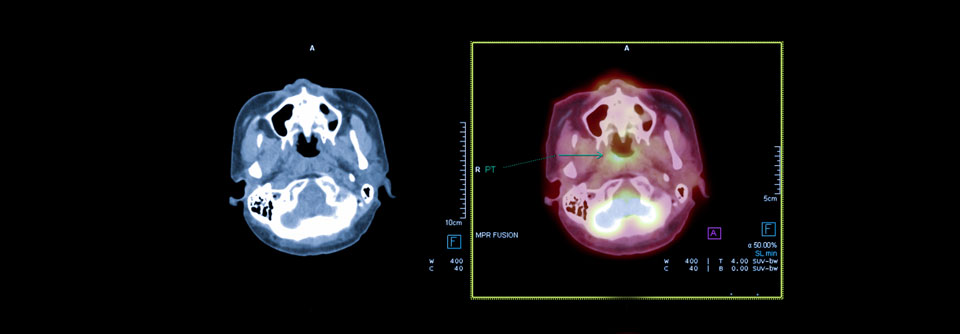

Die Addition von Toripalimab verlängert das progressionsfreie Überleben in rezidivierten/metastasierten Tumoren des Nasopharynx. Die Addition von Toripalimab verlängert das progressionsfreie Überleben in rezidivierten/metastasierten Tumoren des Nasopharynx. © Имя Фамилия – stock.adobe.com

Patienten mit rezidivertem/metastasiertem Nasopharynxkarzinom leben scheinbar länger progressionsfrei, wenn Toripalimab zusätzlich zu einer Chemotherapie gegeben wird. Darauf deuten die Daten der Phase-3-Studie JUPITER-02 hin. Unklar bleibt, welche Rolle die Erhaltung mit dem PD1-Antikörper spielt.